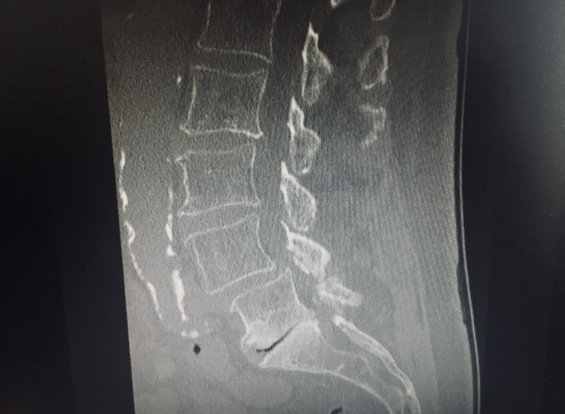

Computed tomography (CT) myelogram 1 month ago showed severe L4-L5 central and foraminal spinal stenosis with complete spinal canal effacement, as well as severe facet arthropathy and multi-level degenerative joint disease (DJD). CT imaging of the lumbar spine taken at that same time is shown in Figure 1.

These changes showed advancement of his disease since prior imaging in 2008. The patient was evaluated by neurosurgery at the time of imaging and was determined to have neurogenic claudication with bilateral L5 radiculopathies with severe L4-L5 central and foraminal spinal stenosis and grade 1 spondylolisthesis (refer to Figures 1 and 2).

Figure 1. Sagittal computed tomography (CT) image demonstrating severe central spinal stenosis and spondylolisthesis.